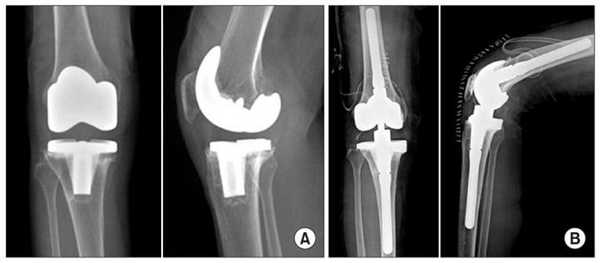

Типы протезов и связанные с ними методики

Вы уже знаете, что бывает полное и частичное эндопротезирование коленного сустава, где в первом случае лечение подразумевает полноценную замену суставных поверхностей, а во втором - имплантацию поврежденного участка одного из мыщелков. Соответственно, протезы классифицируются на тотальные, одномыщелковые и ревизионные для замены импланта.

- После постановки однополюсной системы максимально сохраняется собственный костно-хрящевой сегмент и не затрагиваются связки, кстати, они должны быть в хорошем состоянии.

С каждой последующей операции статистика успешности ниже. Импланты при этом становятся все более громоздкими.

Одномыщелковое протезирование подразумевает срок службы небиологического устройства максимум 7 лет. Тотальное замещение предусматривает время службы вживленного механизма от 15 лет. Ревизионное переносится сложнее, а риск инфекции и других негативных явлений почти в 2 раза выше, чем после первичной операции.